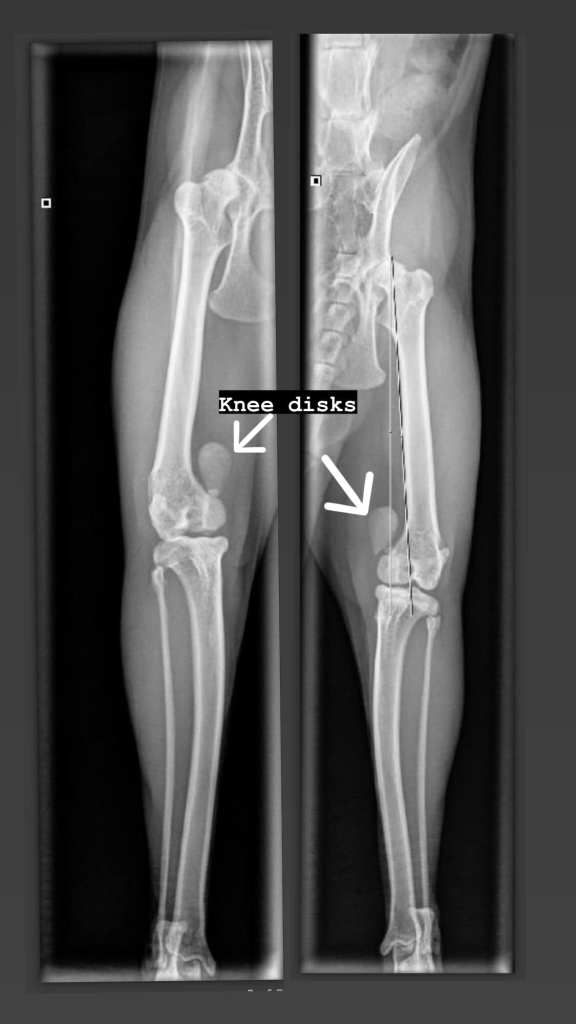

Toen Hummus bij ons kwam, droeg hij een zwaar (medisch) verleden met zich mee. Het vermoeden is dat hij als vok kater in Egypte is gebruikt. Hij had een dubbele graad 4 patella luxatie wat betekent dat zijn knietjeslos aan de verkeerde kant van de benen zaten. Slechts één nier werkte nog, en dat maar voor 40%. Zijn gebit was volledig verrot; elke tand deed pijn. De prognose was allesbehalve rooskleurig. Toch hebben we gekozen om hem te ontzien van zijn tanden om nog een korte, maar goede tijd te hebben.